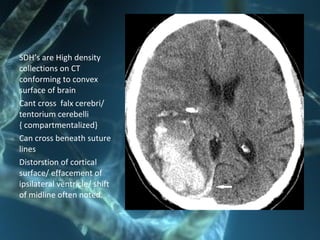

SDH’s are High density

collections on CT

conforming to convex

surface of brain

Cant cross falx cerebri/

tentorium cerebelli

{ compartmentalized}

Can cross beneath suture

lines

Distorstion of cortical

surface/ effacement of

ipsilateral ventricle/ shift

of midline often noted.